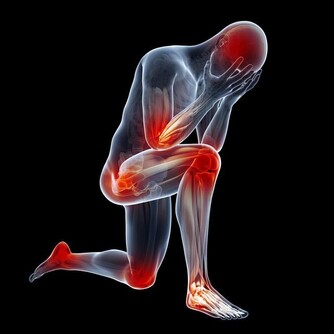

免疫力是人體自身的防禦機制,一個人免疫力低下,就很容易生病,也很容易傳染上疾病。

(1)經常出現輕微的身體不適,如頭疼、牙疼、嗓子疼,或渾身萎靡不振。

(2)平均每月或每兩個月生病一次,包括感冒、發燒、腹瀉等。

(3)近年來開始對某些事物(例如霧霾天氣、貓毛或狗毛)過敏。

(4)上班或者坐地鐵,如果旁邊有人咳嗽、大噴嚏,就很容易被傳染。

(5)換季節時很容易身體不適。

(6)經常臉上長疙瘩,或者口腔潰瘍。

(7)月經不調,或者經期易生病。

(8)經常神經衰弱,異常煩躁、鬱悶,或者夜間稍有動靜就睡不著覺。

免疫力較強的人,上述狀況可能一項也不會出現。而如果你超過3項都符合,那就說明你的免疫力現狀堪憂,有待提升!